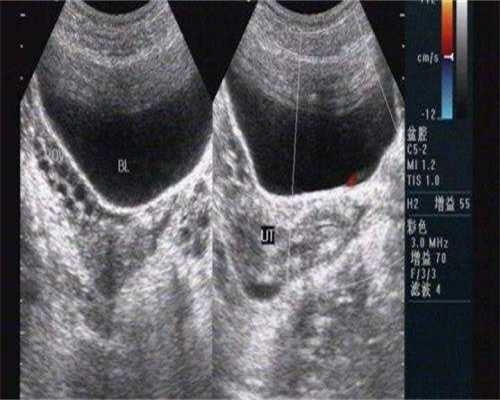

3、胚胎构成后,将其移植回母亲的子宫。假如子宫环境差,如宫腔粘连、子宫内膜息肉、炎症等问题都会影响胚胎着床。因而,为了进步成功的概率,移植前须要合作医师进行相应的评价,发现问题赶快处理。